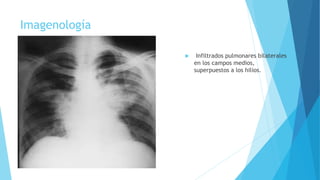

Imagenología

 Infiltrados pulmonares bilaterales

en los campos medios,

superpuestos a los hilios.